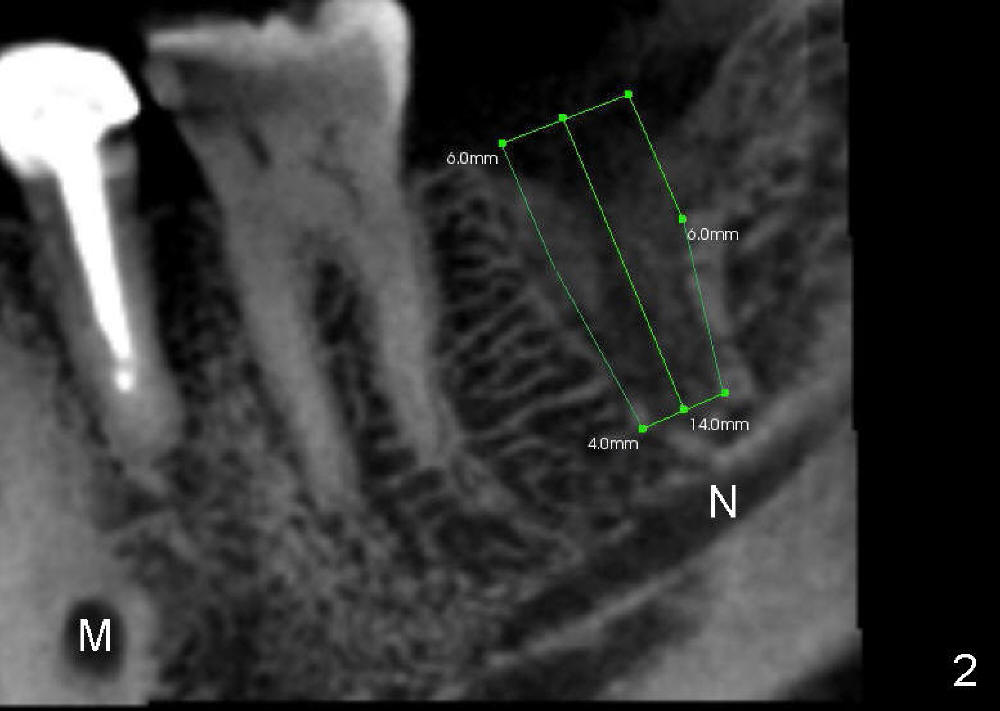

Maia (49 years old) is a typical gagger. She is apprehensive. Preop PA does not show the inferior alveolar nerve (IAN) canal completely (Fig.1 red dashed line). She is willing to get CT, which reveals the relationship between the healing socket and the nerve (N) (Fig.2 (sagittal section), 3 (coronal)). A 6x14 mm tissue-level implant is planned.